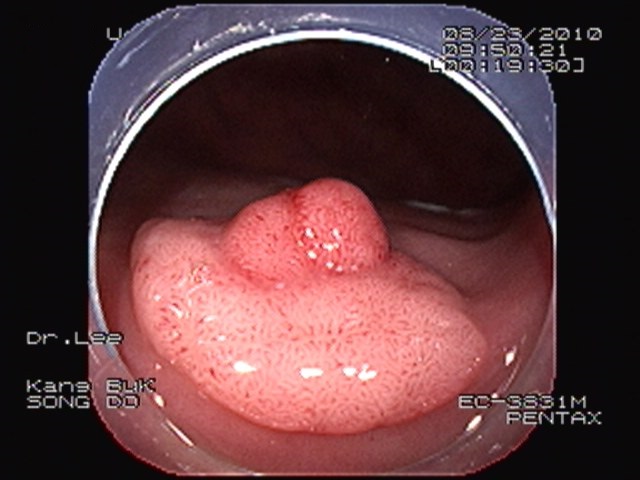

안전한 반수면 대장내시경으로 대장암 예방할 수 있어 최근 들어 수면내시경의 위험성에 대한 많은 보도와 대장내시경 검사에 대한 두려움 때문에, 대장암 조기 진단과 대장암 예방에 꼭 필요한 대장내시경 검사를 피하고 있는 것이 현실이다. 우리나라 사망원인 1위인 악성종양, 자신의 건강과 가족의 행복을 위하여 조기 발견과 예방이 중요하다. 이러한 악성종양 중에서 대장암은 다른 암의 발생과는 구별되는 특징이 있다. 대부분의 대장암은 선종이라는 용종 과정을 지나 악성종양으로 진행되는 선종-암 연속성에 의해서 발생한다. 이러한 선종-암 연속성을 바꾸어 생각해보면, 정기적인 대장내시경 검사로 용종이 발견되었을 때마다 미리 제거한다면 대부분의 대장암은 예방 할 수 있다.

검사 받는 개개인의 상태에 따라서 필요한 최소한의 약제만을 투여하여, 불안과 고통을 없애주면서 검사 도중에 같이 화면을 보면서 설명을 들을 수 있는 반수면 대장내시경 검사를 시행하고 있다. 또한 최소한의 약제를 투여함으로써 빠른 일상으로의 복귀가 가능하다. 강북송도외과 이종호 원장은 “대장내시경 검사는 고통스럽다는 소문 때문에, 대장내시경 검사를 원하는 분들은 아주 깊은 수면 상태에서 검사 받기를 원하고 있다. 따라서 아주 드물지만 원하지 않았던 불행한 결과를 초래하는 경우가 있을 수 있다. 하지만 수면내시경의 목적은 깊은 수면에 있는 것이 아니라 편안한 검사를 위한 하나의 방법일 뿐이다. 불안과 고통을 덜어주는 정도 만의 진정을 유지하면 안전하면서 편안한 검사를 시행할 수 있는 것이다”고 말했다. 강북송도외과에서 최근 시행한 대장내시경 검사 2,122건의 예를 검토한 결과, 전체 검사자의 45.8%에서 대장암의 원인이 되는 선종이 발견되었으며, 비교적 젊은 연령대인 20대에서 12%, 30대의 15%에서 선종이 발견되고 있어 자세하고 철저한 정기적인 대장 검사가 필요하다는 것이다. 한국 유로저널 이인규 의학전문 기자 eurojournal02@eknews.net